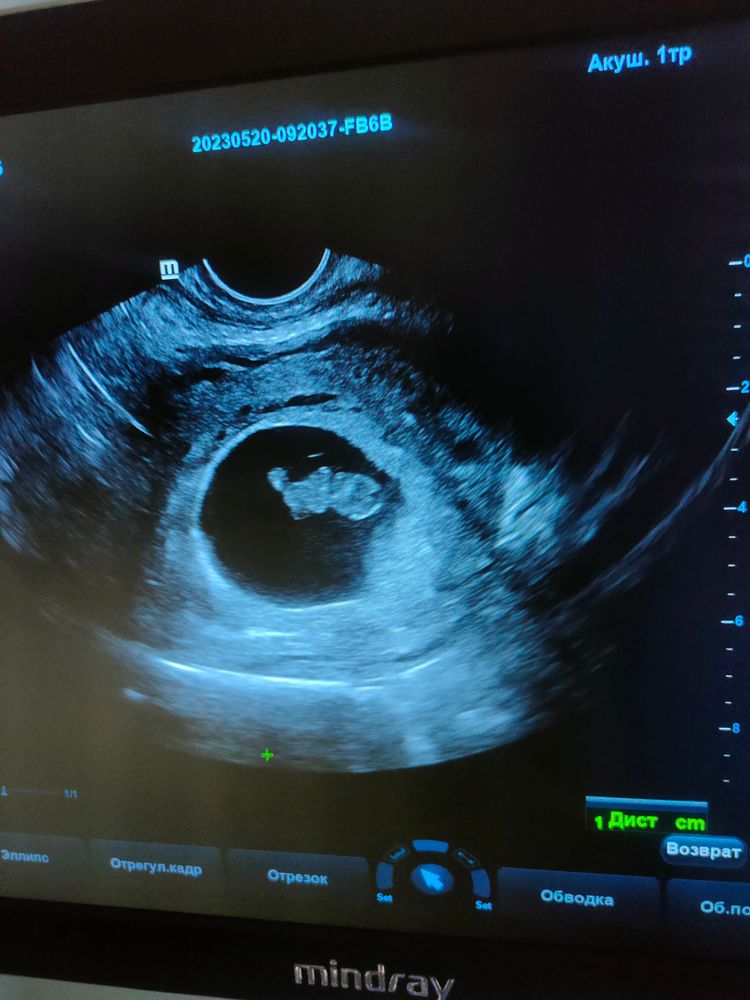

Второе УЗИ 8 нед.2 дня

УЗИ, КТГ, доплерСделала узи срок по М. 8н1д , по узи 8н2д

. Прям все как надо , растет бусинка моя . Такая уже большая на фото , чего то там капашится , сердечко бьется . Так мило было смотреть , столько эмоций ♥️

Пдр поставили на 31.12 .